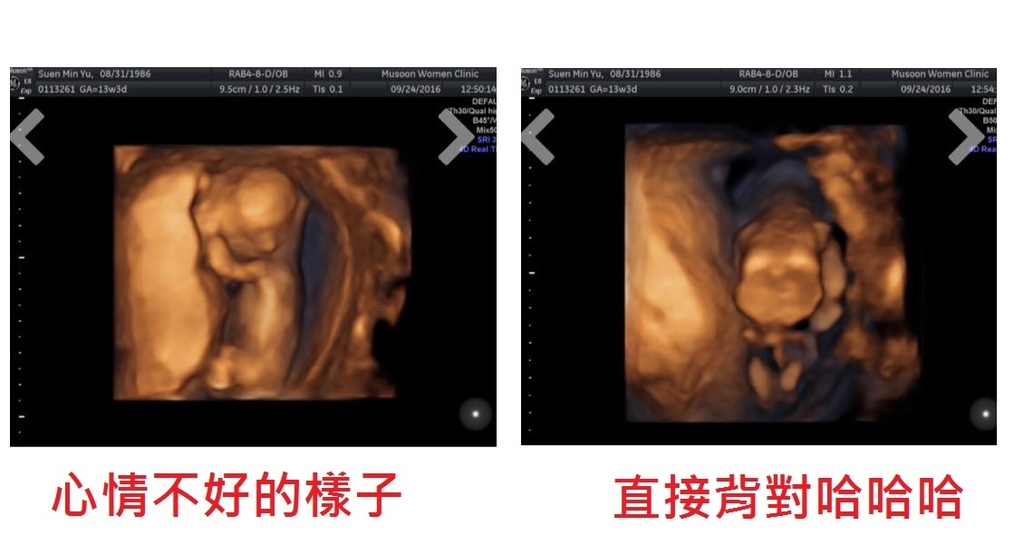

13W3D的寶寶心情似乎不太好,一直遮著臉不讓我們看

最後還索性背對,直接露屁股給我們看